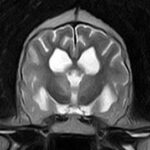

頻繁に嘔吐・下痢をするワンちゃんの精密検査依頼で内視鏡検査のご紹介がありました。内視鏡検査で上部・下部消化管を検査し、粘膜を採取し病理組織検査に出しました。結果は「胃:らせん菌感染を伴う慢性胃炎(中程度)/結腸:慢性腸炎(軽度)」とのことでした。その後かかりつけの先生のところ […]